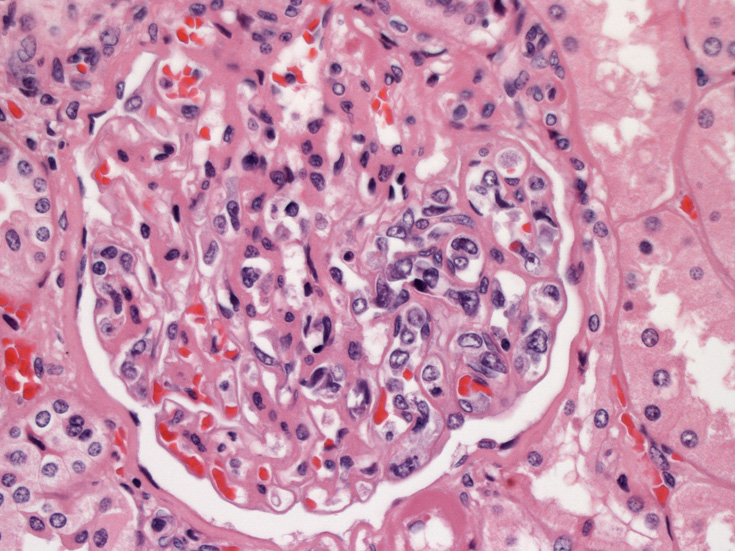

腎臓;糸球体係蹄内に腫瘍細胞が増殖するほか細腎動脈にもみとめられる。